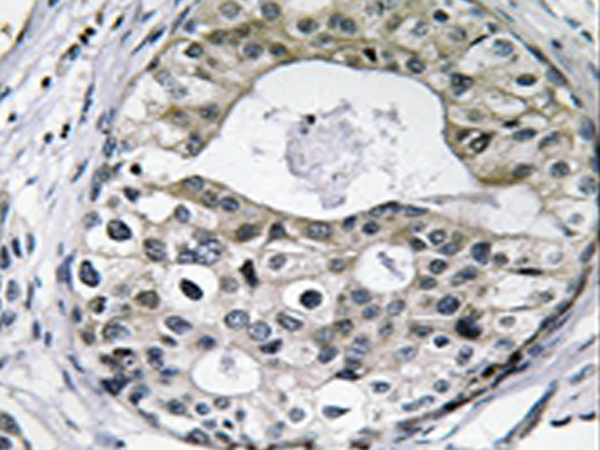

IHC positive control: |

Human breast carcinoma tissue |

IHC Recommend dilution: |

50-100 |